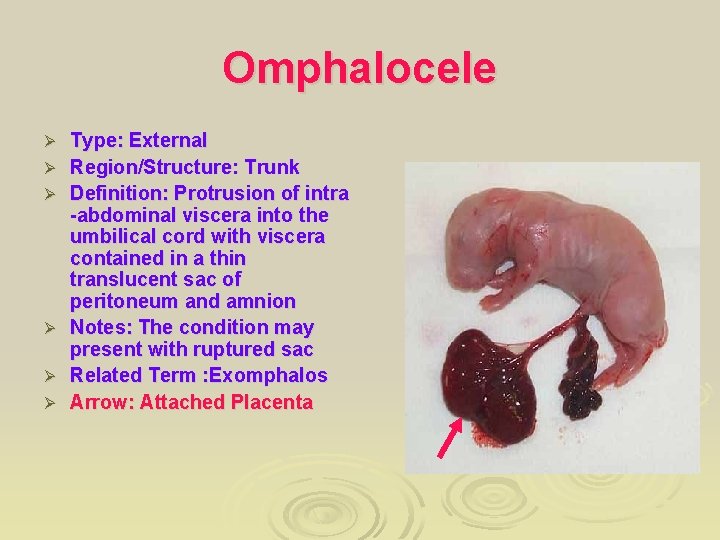

Omphaloceole Ø Result from a median defect of the abdominal muscles, fascia, and skin at the umbilicus Ø Herniation of intra-abdominal structure liver and intestine into the proximal end of the umbilical cord Ø It is covered by a membrane composed of peritoneum and amnion

Omphalocele Ø Ø Ø Type: External Region/Structure: Trunk Definition: Protrusion of intra -abdominal viscera into the umbilical cord with viscera contained in a thin translucent sac of peritoneum and amnion Notes: The condition may present with ruptured sac Related Term : Exomphalos Arrow: Attached Placenta